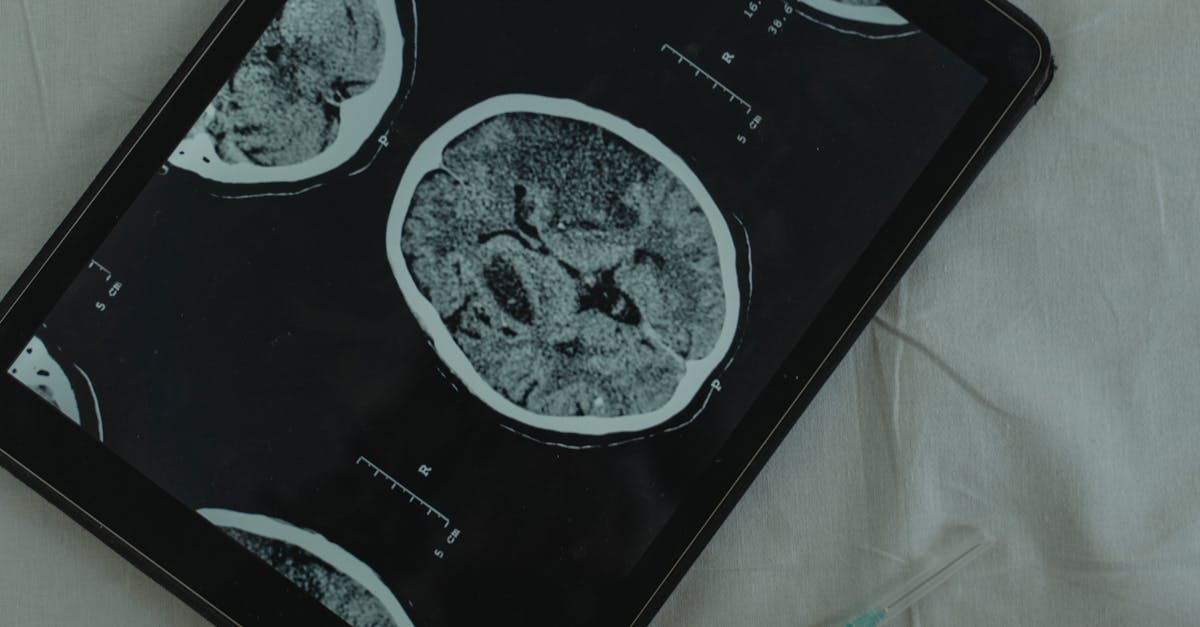

In addition to genomic analysis, neuroimaging techniques play a crucial role in neurogenetics research. Functional magnetic resonance imaging (fMRI) and positron emission tomography (PET) help visualize brain activity in real-time, enabling researchers to link genetic variations with specific brain function and behavior. Behavioral assessments complement these methods, allowing scientists to quantify responses and changes in behavior in alignment with genetic data. This multidisciplinary approach deepens understanding of how genetic factors and neurological function interact to shape behavior across different contexts.

Another vital technique is the application of neuroimaging technologies, such as functional magnetic resonance imaging (fMRI) and positron emission tomography (PET). These methods enable researchers to visualize brain activity and structure in relation to genetic variations. By correlating patterns of brain activity with behavioral data, scientists can identify neural circuits influenced by genetic factors. Additionally, advancements in gene editing, particularly CRISPR technology, allow for precise modifications of specific genes in model organisms, facilitating the exploration of how genetic alterations impact behavior on a molecular level.